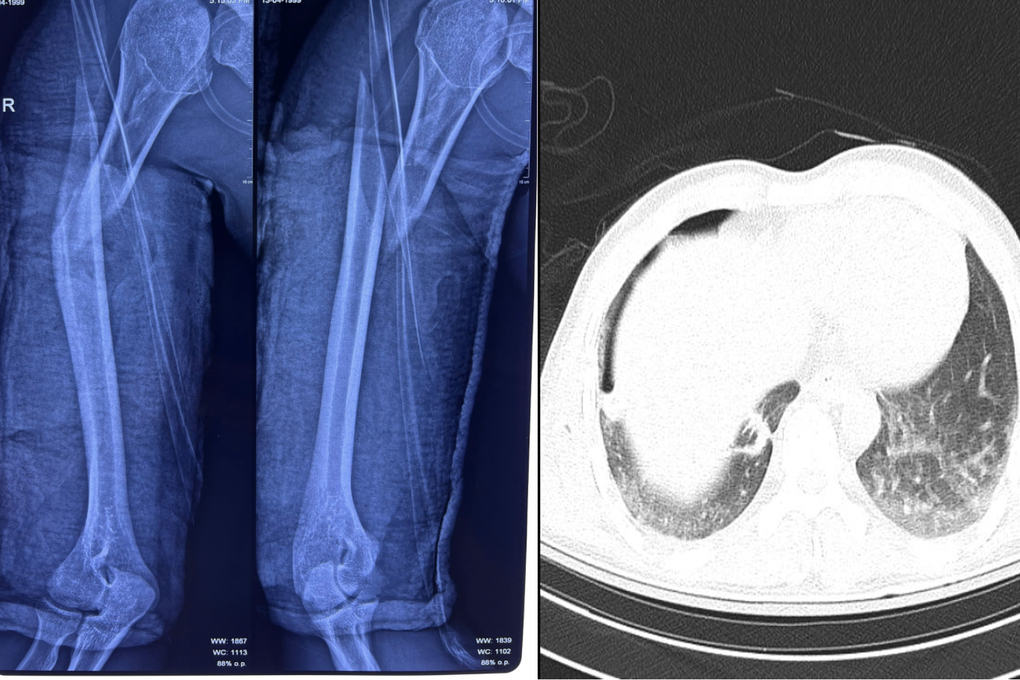

Kết quả chụp X-quang ngực tại giường cho thấy nam thanh niên bị tràn khí màng phổi phải do chấn thương dập phổi nặng, kèm gãy phức tạp đầu trên và gãy chéo dài 1/3 trên xương cánh tay phải”, BS.CKI Sơn Tấn Ngọc, khoa Chấn thương chỉnh hình cho biết.

Xương cánh tay phải của người bệnh bị gãy hoàn toàn, kèm dấu hiệu tràn khí màng phổi (Ảnh: BVCC).